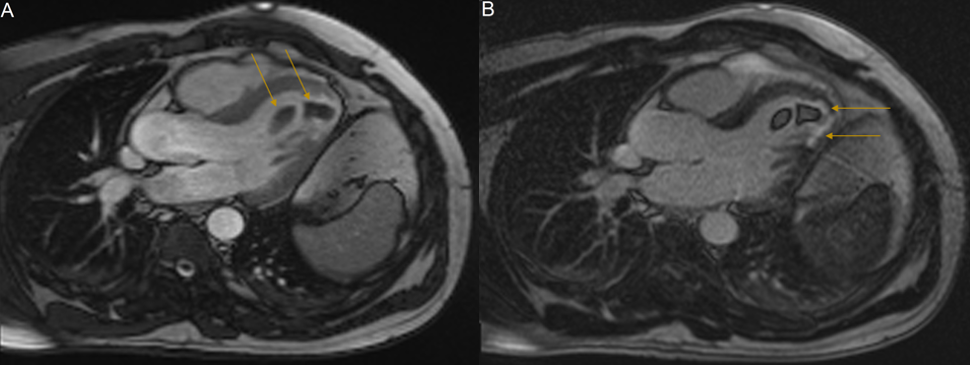

A 42-year-old Greek male concreter presented to hospital with bilateral acute lower limb claudication. He reported incidental episodes of transient dysarthria in the three weeks prior. Otherwise, he had no significant past medical history. Acute lower limb ischaemia due to arterial occlusion was suspected. Lower limb and abdominal and pelvic angiography demonstrated complete occlusion of the popliteal arteries bilaterally, and subtotal occlusion of the left common femoral and right common iliac arteries, due to thrombo-emboli. He subsequently underwent embolectomy, with complete resolution of his lower limb symptoms. Investigations to elucidate their source were performed. Transthoracic Echocardiography (TTE) revealed mild segmental apical systolic dysfunction with two sizeable mobile LVT, one attached to the apical septal wall; and one attached to the mid-inferior septal wall, with an additional smaller thrombus attached posteriorly. These were in close apposition to one another. This radiology is depicted in Figure 1. CMRI demonstrated left ventricular wall thinning and hypokinesis, and transmural LGE. These findings were consistent with previous MI and are depicted in Figure 2. The masses demonstrated T2-weighted signal hypointensity and an absence of LGE; findings consistent with LVT. Cerebral magnetic resonance imaging demonstrated bilateral cortical T2 and Fluid-Attenuated Inversion Recovery (FLAIR) hyperintensities with concomitant restricted diffusion. These were thought to be representative of multi-territory cardio-embolic infarcts.

Figure 2: : Cardiac MRI, long axis three-chamber view. (A): Cine sequence image demonstrating two low-signal intensity apical masses, indicated by yellow arrows. Cine imaging demonstrates hypokinesis of the left ventricular apical cap, the apical septum and the apical-inferior segment suggestive of completed myocardial infarction. (B): LGE-MRI sequence. The absence of gadolinium enhancement of the apical masses is characteristic of intraventricular thrombi. Note the enhancement of the thinned apical region consistent with myocardial scarring (yellow arrows). Abbreviations: LGE: Late Gadolinium Enhancement; MRI: Magnetic Resonance Imaging.